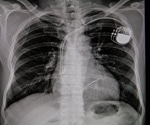

Is generative AI the future of rapid and accurate chest radiograph interpretation in the ER?